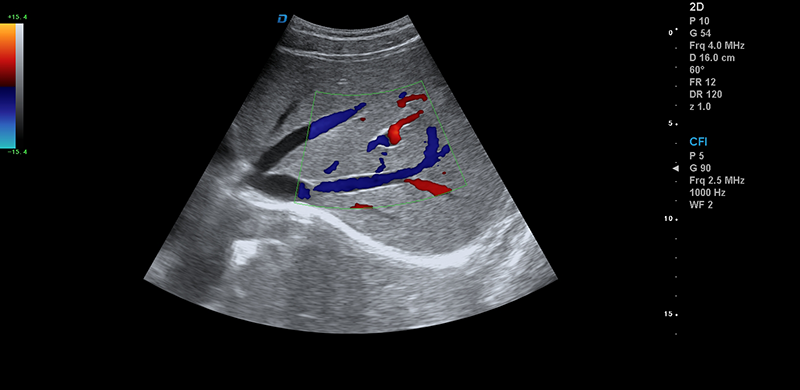

●能量多普勒成像(PDI)

●方向性能量多普勒(DPDI)

●B/C/D三實時成像